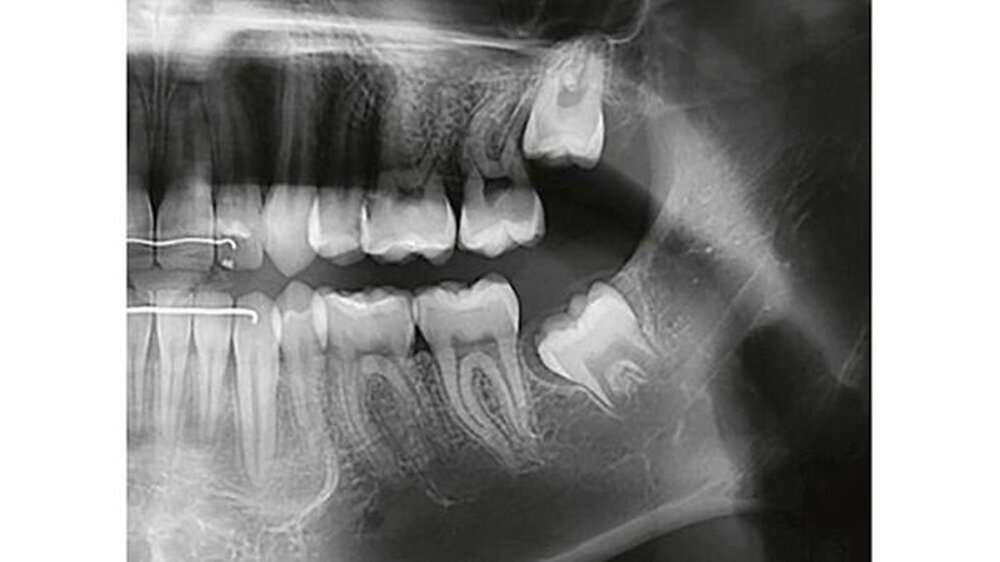

Auf dem mitgelieferten vier Jahre zuvor erstellten Orthopantomogramm (OPT) waren noch keine Hinweise auf das Vorhandensein einer Veränderung regio 32-34 sichtbar (Abbildung 2). Ein Jahr später konnte anhand des OPT bereits eine radioopake Struktur regio 33, 34 festgestellt werden (Abbildung 3). Auf dem aktuellen OPT und digitalen Volumentomogramm (DVT) zeigten sich regio 32-34 lingual multiple, rundliche, unterschiedlich große Radioopazitäten, umgeben von einer radioluzenten Zone.